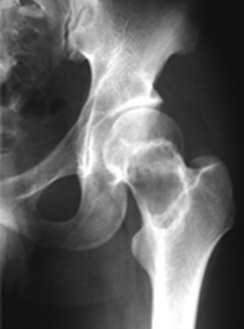

▌硬化缘

地图样破坏或膨胀性破坏边缘显示宽窄不等的反应硬化带,使病变与正常骨形成明显的边界。硬化缘宽窄与肿瘤生长速度及病程长短有关,一般而言,肿瘤生长缓慢病程较长者其硬化缘较宽,反之,生长较快发生不久的肿瘤硬化缘较窄,硬化缘的宽窄可以从一个侧面反映肿瘤的生物学特性。有硬化缘者主要见于良性肿瘤(图 47、图 48、图 49),少数也可见于恶性程度不高的恶性肿瘤(图 50)。无硬化缘多见于侵袭性和恶性肿瘤。

图 50.硬化缘:甲状腺滤泡型癌骨转移